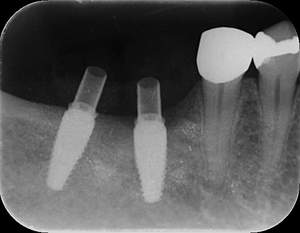

レントゲン写真

- 透過像

| 年齢 | 50代・男性 |

|---|---|

| 主訴 | 右下歯が疼く |

| 治療内容 | ・右下6番インプラント ※1:FGG(遊離歯肉移植術)とは、足りない歯ぐきを上顎から上皮を切り取り移植する外科手術 |

| 治療費 | 合計:902,000円(税込) ■内訳 |

| 治療期間 | 9ヵ月 |

| 治療方針 | 右下の当該歯は歯根破折により保存不可能と診断しました。歯周疾患も伴っていたため抜歯後に骨吸収※1が大きく起こることが予測できました。チタンメッシュ併用骨再生誘導法(GBR※2)を選択しインプラント埋入と同時に行い自然な歯槽骨のラインを再現しました。またGBRを行う際にインプラント辺縁の付着歯肉の減少が起こる為、遊離歯肉移植術(FGG※3)を行い清掃性を考慮した形態に仕上げました。 ■治療方針の解説 治療した右下の歯をレントゲンで撮影したところ根本の部分に黒く写る箇所があり「根尖性慢性周囲炎※1」と診断。また歯周病も進行していました。 ※1 骨吸収・・・歯槽骨という歯を支える骨がなくなっていくこと |

| 担当者所見 | 主訴の右下だけでなく歯茎の腫れ、発赤があり不良補綴や不良充填など他にも治療箇所が多数ありました。プラークコントロールが不良であった為まずはブラッシング指導を行いセルフケアの重要性を理解していただくところからスタートしました。 右下6番の歯はインプラント治療を行なった結果審美的にも機能的にも患者様の満足を得ることができました。骨造成と歯肉移植も行なった為インプラントを支える十分な歯周組織の獲得ができたと思っております。 |